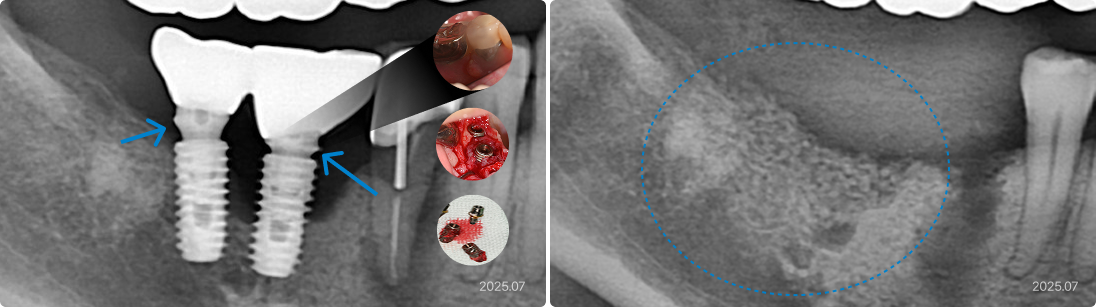

56세, 남치과 폐업으로 사후 관리 부재

“임플란트가 다 망가지고 빠졌어요. 남은 것도 흔들리고 아픈데,

치료받았던 치과가 없어졌어요.”

• 치료 받은 치과의 폐업, 사후 관리가 안됨

• 임플란트 주위 염증 장기간 방치

• 잇몸 뼈가 녹아서 없어지고 임플란트 빠짐

치료 후

• 문제가 생길 가능성을 최소화한 위치에 충분한 수의 임플란트 식립

• 정기적인 검진과 관리로 합병증 조기에 차단